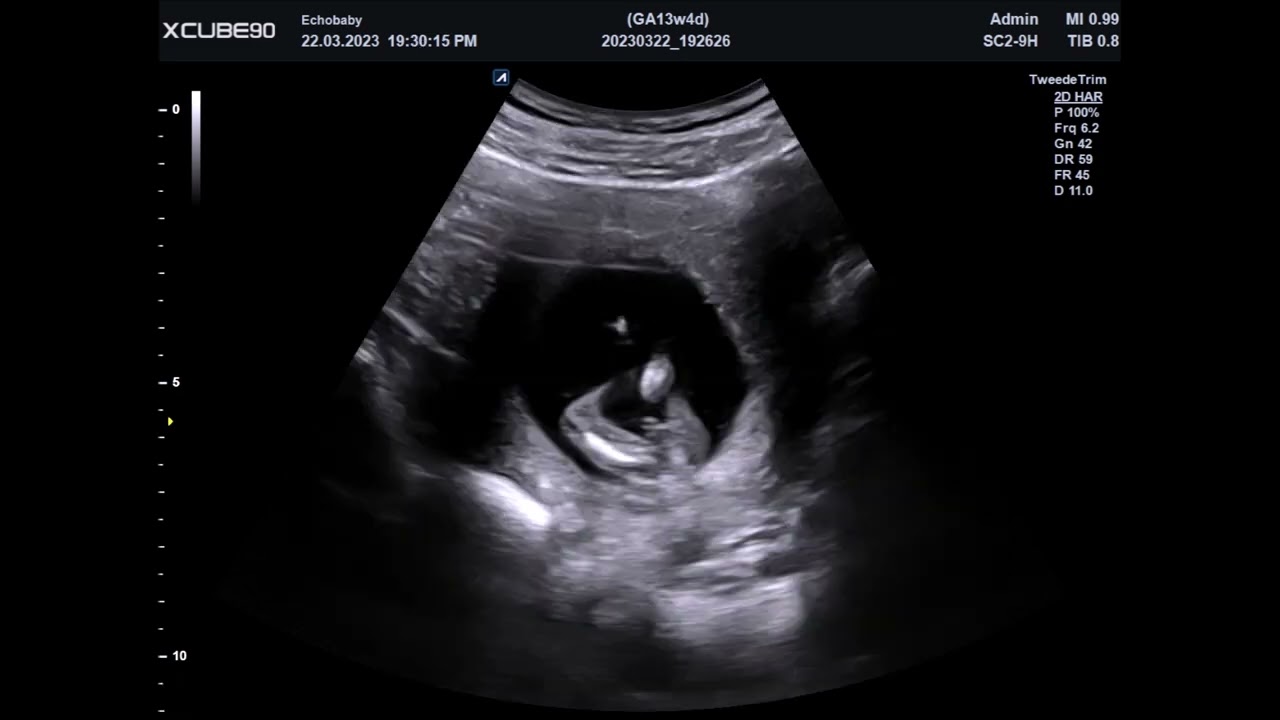

Echo 13 Weken Geslachtsbepaling, Foto's Jongens

Echo 13 weken geslachtsbepaling, foto's met jongens. Deze echo geslachtsbepaling bestaat uit foto's van jongens van 13w2d tot 13w6d.  Op sommige foto's staat er een pijltje bij of staat het bijgeschreven.  Op andere foto's zal je het zelf moeten ontdekken.  Lukt dat?